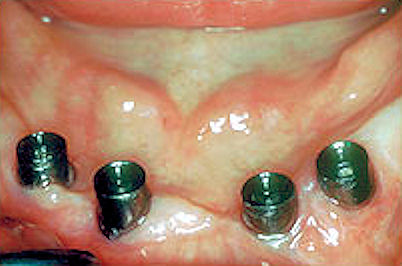

Standard abutments connected to the tops of the implants